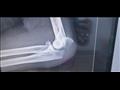

أجرى الفريق الطبي لجراحة العظام بمستشفى أبو رديس العام بجنوب سيناء، جراحة عاجلة لمصاب في حادث سير، يعاني من كسر بعظمة الزند وكسر مضاعف برأس عظمة الكعبرة في الكوع.

وأوضح وكيل وزارة الصحة أن الفريق الطبي بمستشفى أبورديس استقبل المصاب، وجرى تجهيز غرفة العمليات، لإجراء عملية جراحية عاجلة، وتثبيت عظمة الزند بمسامير.